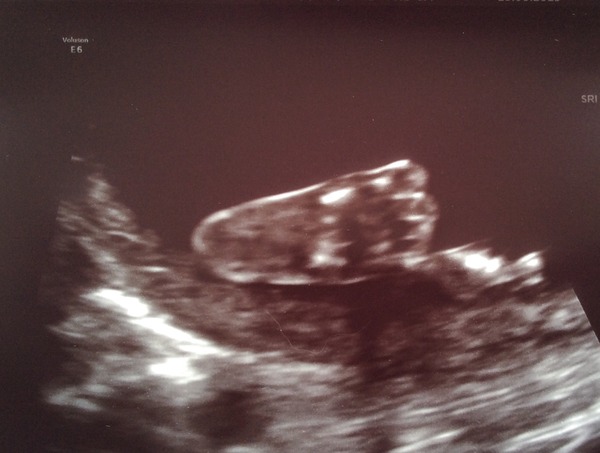

For those not on FB (how many is that now btw?)

Our sonographer was ace, how about this for a scan photo. Boy or girl?

Jan 16 #9 halfway point - time to watch our bumps grow 